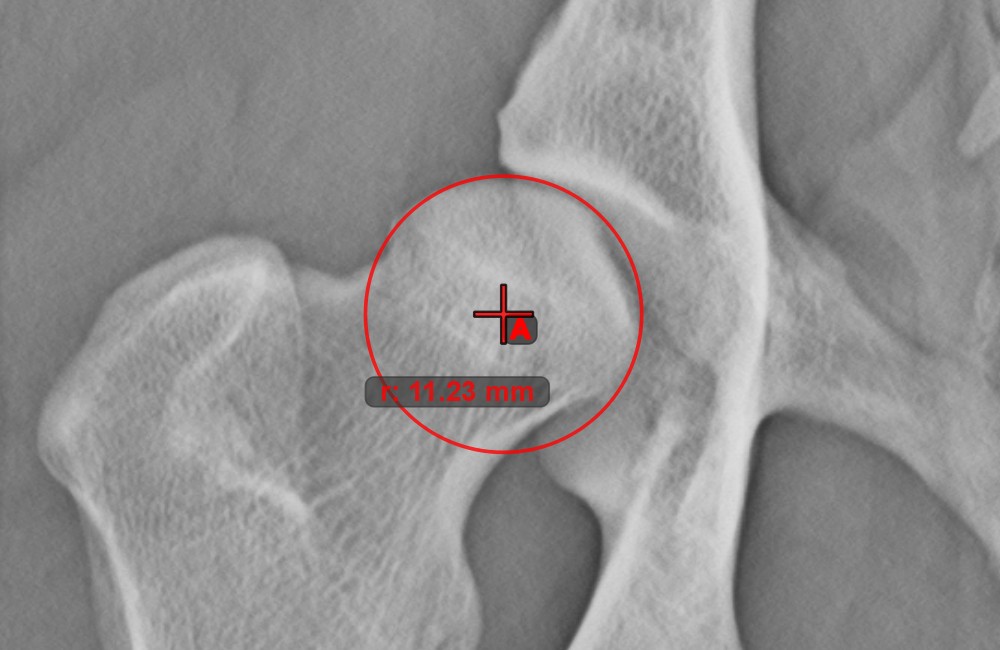

Circle with Defined Radius¶

Draw a circle with fixed radius by using the Circle with Defined Radius tool. Only the position of the circle on the scene can be modified later.

Select the tool from the left toolbar and assign it to one of the available mouse buttons. Place the origo of the new circle on the scene or select an already existing point. Specify the desired radius of the circle and press OK

to complete the measurement.